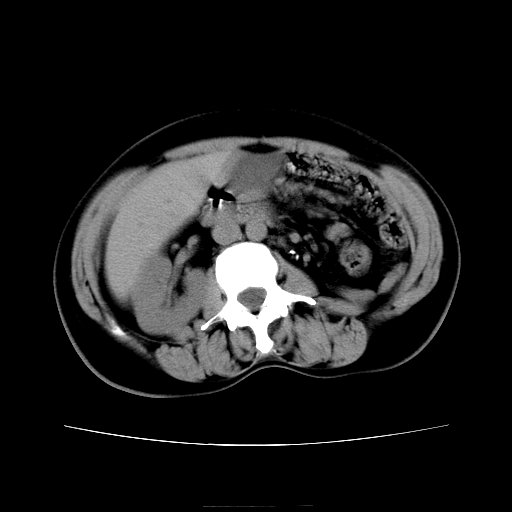

女45y多次(7次)碎石,结果不理想!曾碎石后尿出小碎石,仍腰痛,要求ct,其它不详.本人更倾向于钙化斑!无肾实质破坏,积水等提示集合系统无梗阻.另外腹腔多处钙化.是否结核后改变!谢谢赐教!

1)双肾结石。2)脾脏钙化灶。3)腹膜后多发淋巴结钙化。

尿路结石与腹部淋巴结钙化共存,建议v尿路造影检查,免得钙化灶冤枉为结石受罚。

考虑双肾结石,肾脏实质无破坏表现,没有结核病史,不考虑肾结核,